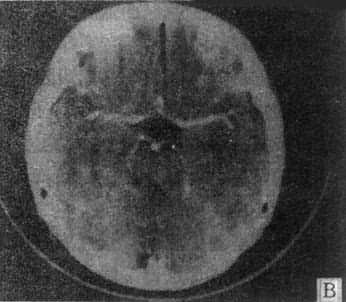

(二)脑梗塞 CT表现与梗塞类及病期有关,分述如下。

1.缺血性脑梗塞 脑血管闭塞后24小时内,CT可无阳性发现。以后则出现低的或混杂密度区,累及髓质和皮质,多为楔形和不整形,边缘不清。常并发脑水肿和占位表现,1~2周后边缘变清楚,2~3周后病灶变成等密度,与脑水肿消失和巨噬细胞反应有关。4~6周则变为边缘清楚,近于脑脊液密度的囊腔,病侧脑室扩大。脑梗塞3天至6周时于低密度区中可出现脑回状,斑状或环状增强,多在皮质,也见于髓质。增强同脑梗塞后修复反应性新生血管长入有关,而血脑屏障破坏,造影剂血管外渗则是次要的。

MRI 适宜于观察CT扫描为等密度的亚急性脑内血肿,已如前述。脑梗塞的发现MRI比CT扫描要早,一般起病后6小时MRI即可出现异常。脑干和小脑腔隙性梗塞灶的探测,MRI明显优于CT。脑梗塞灶在T1WI上呈低信号,在T2WI上呈高信号(图5-1-6C、D)。

图5-1-6 MRI扫描SE序列图像

在矢状面(A)和冠状面(B)T1WI可见垂体肿块向鞍上延伸,呈等信号区(→);在横断面T1WI(C)和T2WI(D)上分别可见左枕和右基底节区脑梗塞灶呈低和高信号区(→);在矢状面T1WI(E)和横断面T2WI(F)上,可见基底动脉瘤环形影,其内为低信号和高信号区,高信号区为瘤内血栓形成(→)